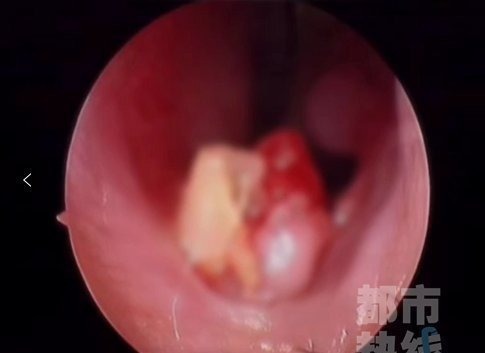

近日,西安市第三医院接诊了一位6岁女童患者。孩子的鼻腔不适,通气不好。为孩子进行仔细查体后,医生发现在她的左侧鼻腔底部有一白色凸起,触之质硬。检查后所有人都惊呆了CT片子上显示在孩子的左侧鼻腔里竟然有一个白色高密度异物影一颗牙

随后,医院为孩子安排了手术!医生剥开女孩鼻腔里牙齿周围的粘膜,在鼻腔狭窄的空间里,将这颗“失联”了三年的牙齿完整拔出,所幸术后孩子恢复良好。